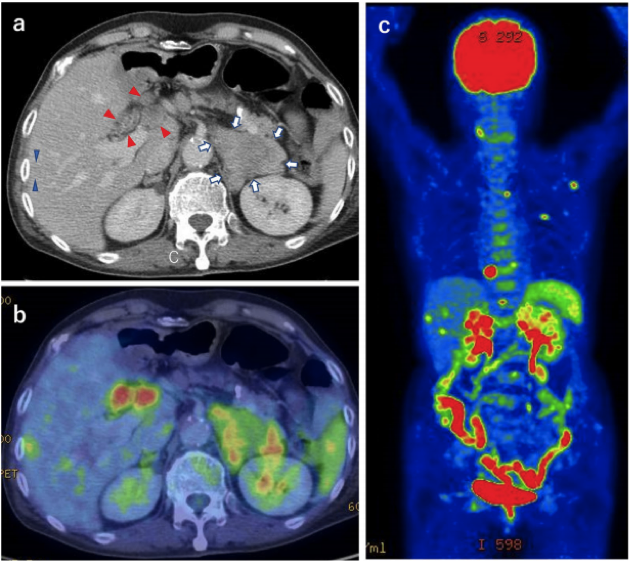

腹部超声显示肝脏多发结节。计算机断层扫描(CT)显示,左侧肾上腺有一个60mm的肿块,肾动脉和肝总动脉周围的淋巴结肿大,肝右叶有多个结节(图1a)。正电子发射断层扫描(PET)显示,氟脱氧葡萄糖F18在与CT所见病灶相同的区域,以及在左肩胛骨、左第六肋骨和第九胸椎左侧突起的积聚增加(图1b,c)。根据这些发现,放射科医生怀疑肾上腺癌在全身有多处转移。此后,患者出现发烧,获得两组血培养物。三天后检测到革兰氏阳性杆菌。将细菌与含5%羊血的胰蛋白酶大豆琼脂传代培养,经鉴定为单增李斯特菌。

图1. 患者的影像学发现